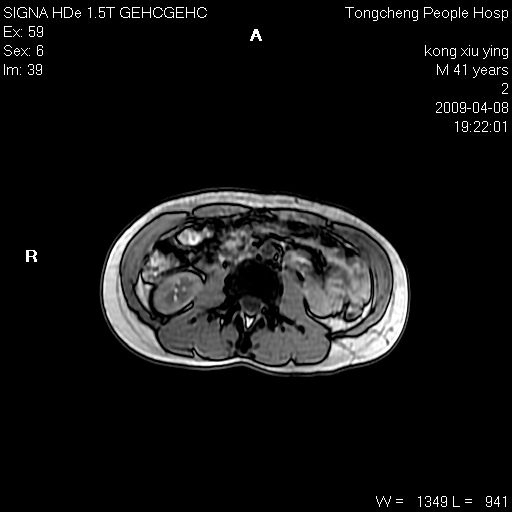

标题: CL1008:【经典】胆囊石榴籽样结石。 [打印本页]

标题: CL1008:【经典】胆囊石榴籽样结石。

女,41岁。健康体检——彩超提示:胆囊显示不清。平素健康,无不适感。

腹部mr扫描及mrcp,图像如下: